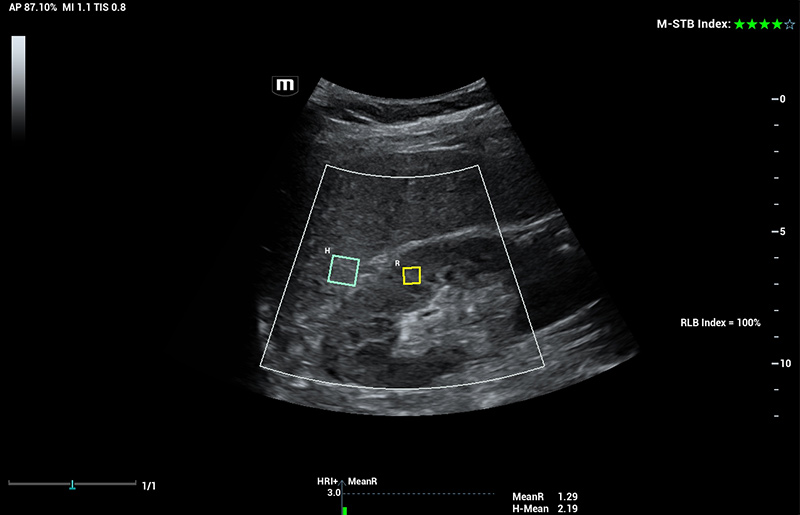

Com tecnologia ZST+

A plataformaZST+ representa um salto extraordinĂĄrio na tecnologia de ultrassom, passando da tradicional forma??o de feixe para o processamento de dados de canal. Essa inova??o revolucionĂĄria supera as compensa??es tradicionais entre resolu??o espacial, resolu??o temporal e uniformidade do tecido, resultando em uma qualidade de imagem inigualĂĄvel com infinitas solu??es de gera??o de imagens.

O Resona I9 fornece solu??es clĂnicas abrangentes para aplica??es dedicadas. Com base em percep??es aprofundadas em diferentes cenĂĄrios clĂnicos, ele oferece inova??es que fornecem aos usuĂĄrios extrema clareza, inteligĂȘncia excepcional e confian?a excepcional no diagnĂłstico.